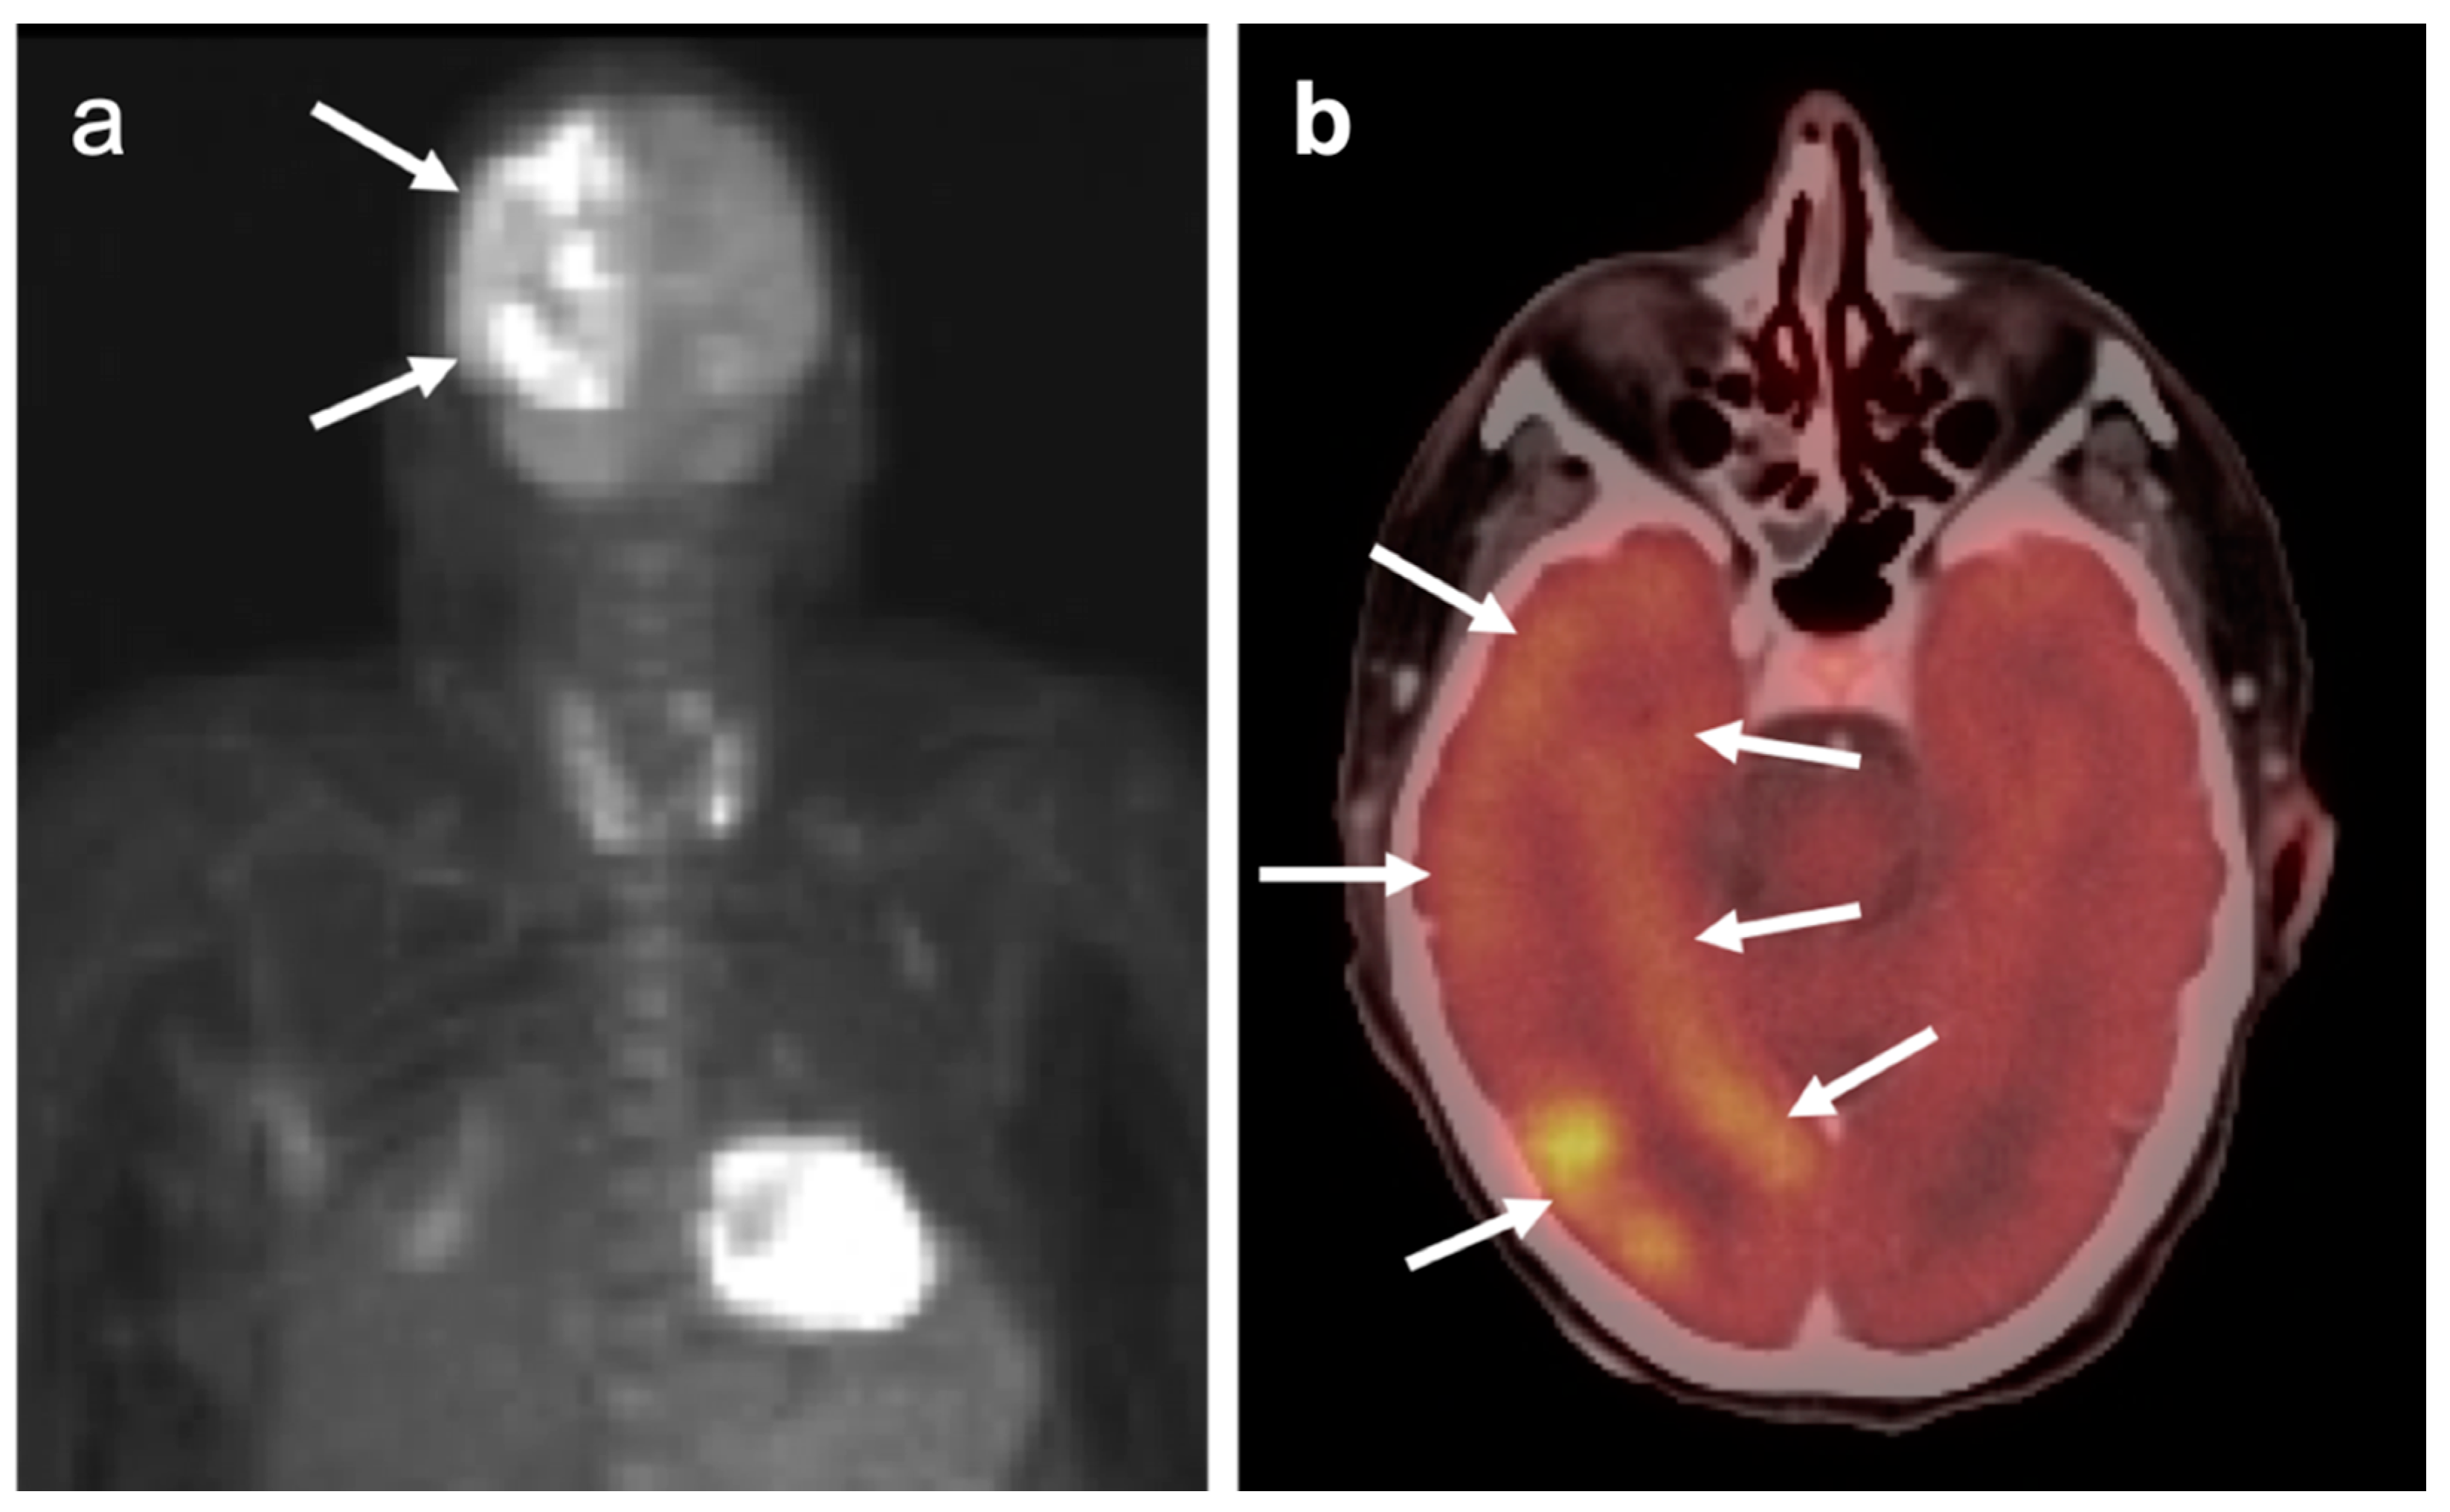

2.3. Nasopharyngeal Carcinoma

- Mohandas, A.; Marcus, C.; Kang, H.; Truong, M.-T.; Subramaniam, R.M. FDG PET/CT in the management of nasopharyngeal carcinoma. AJR Am. J. Roentgenol. 2014, 203, W146–W157. [Google Scholar] [CrossRef]